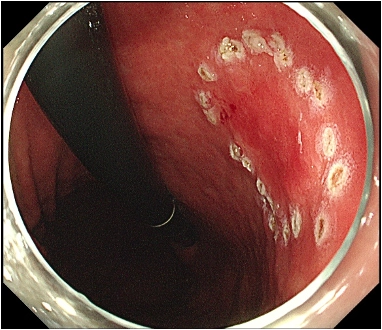

図1: 病変はやや発赤調の領域(矢印)としてわかる様子(サンプル)

図1. 病変はやや発赤調の領域(矢印)としてわかります。